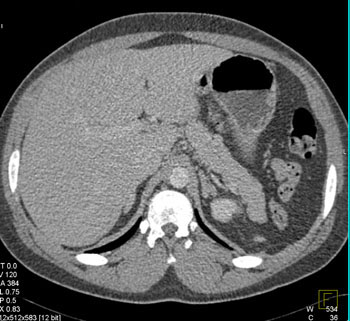

Over half of pulmonary artery sarcomas are misdiagnosed as chronic pulmonary thromboembolism based on their almost identical radiographic findings . Furthermore, the usual presenting symptoms of pulmonary artery sarcoma are dyspnea, chest pain, cough or hemoptysis, which also make the lesion clinically indistinguishable from pulmonary thromboembolism. With difficult clinical and radiographic diagnosis, the tumors are often incorrectly managed and ultimately diagnosed upon surgical treatment for presumed thromboembolic disease . References: - Mandelstamm M (1923) Ueber Primaeren Neubildungen des Herzen. Virchow Arch Path Anat 245: 43-54.

Here is a case that was a true saddle pulmonary embolism. Note some of the key differences between the two cases are that the tumor fills in the entire vessel with no wall seen.

Saddle pulmonary embolism |